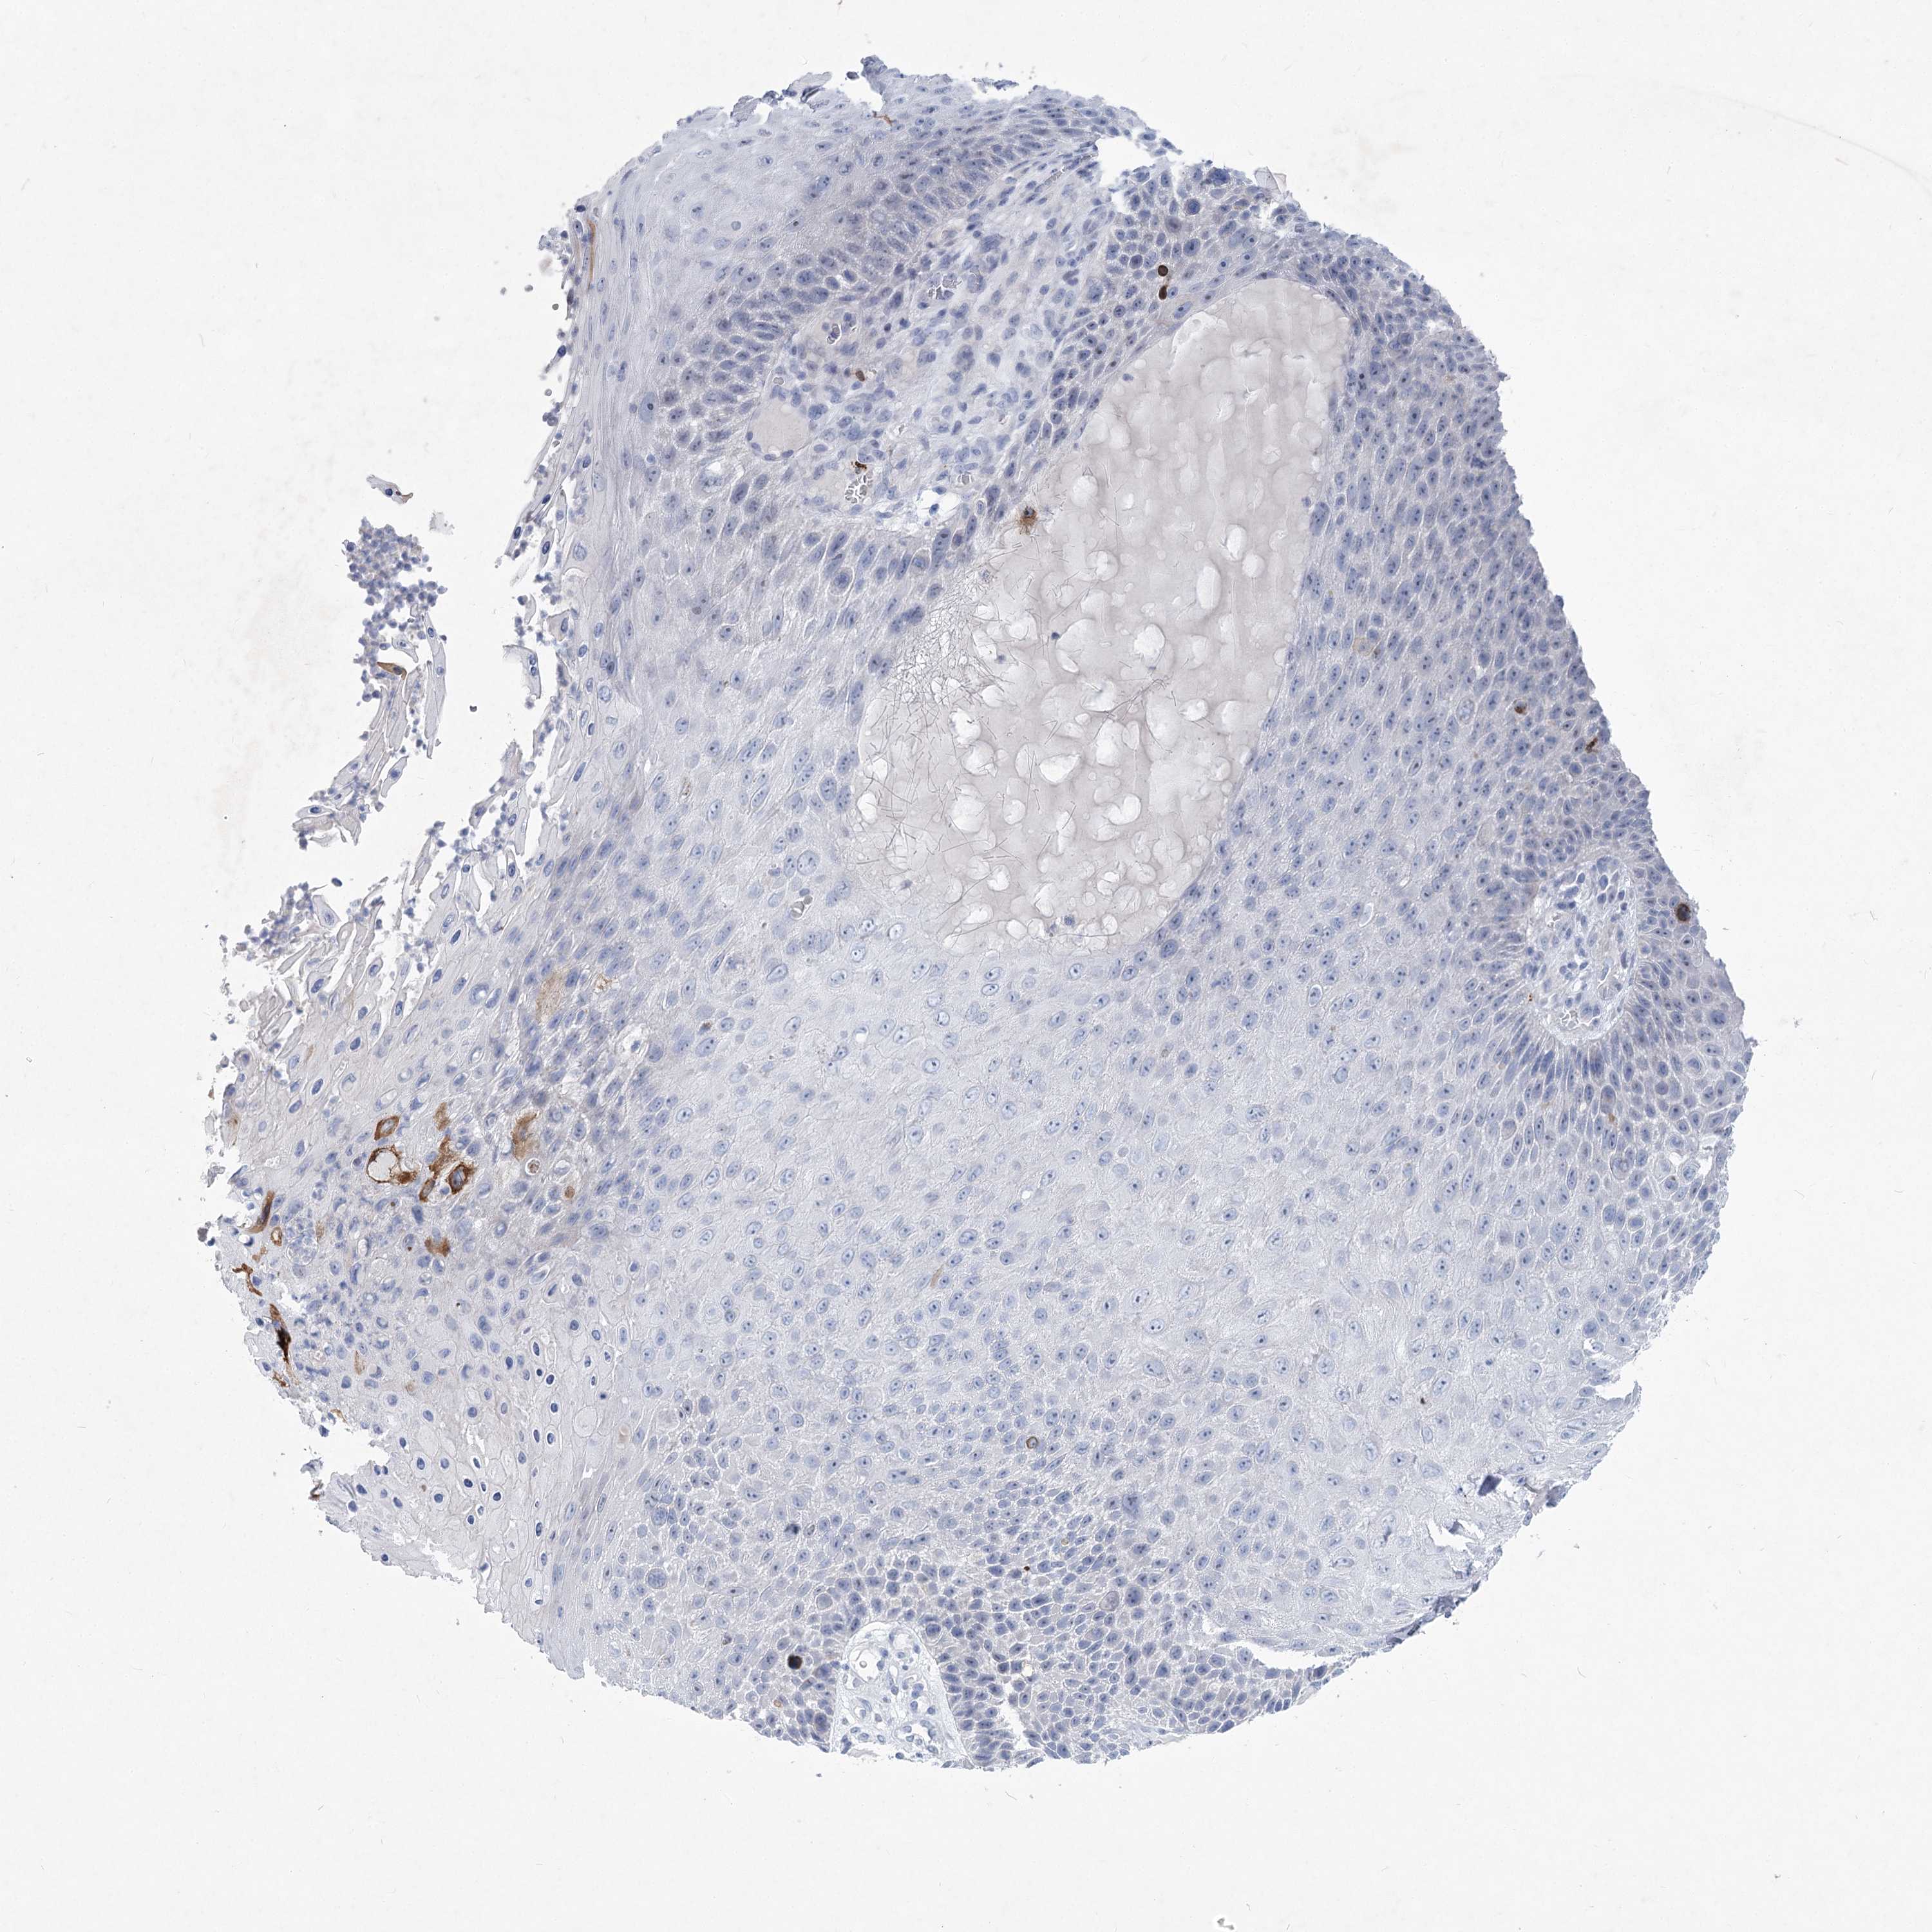

Basal cell and squamous cell cancer

SKIN CANCER - Protein expressioni

A mouse-over function shows sample information and annotation data. Click on an image to view it in a full screen mode. Samples can be filtered based on level of antibody staining by selecting one or several of the following categories: high, medium, low and not detected. The assay and annotation is described here.

Antibody stainingi

Antibody staining in the annotated cell types in the current human tissue is reported as not detected, low, medium, or high, based on conventional immunohistochemistry profiling in selected tissues. This score is based on the combination of the staining intensity and fraction of stained cells.

Each image is clickable and will lead to virtual microscopy that enables deeper exploration of all samples and also displays staining intensity scores, fraction scores and subcellular localization as well as patient and tissue information for each sample.

Antibody HPA037795

Antibody HPA038419

Staining

High

Medium

Low

Not detected

Intensity

Strong

Moderate

Weak

Negative

Quantity

>75%

75%-25%

<25%

None

Location

Nuclear

Cytoplasmic/membranous

Cytoplasmic/membranous,nuclear

Basal cell carcinoma

Squamous cell carcinoma, NOS

Squamous cell carcinoma, metastatic, NOS